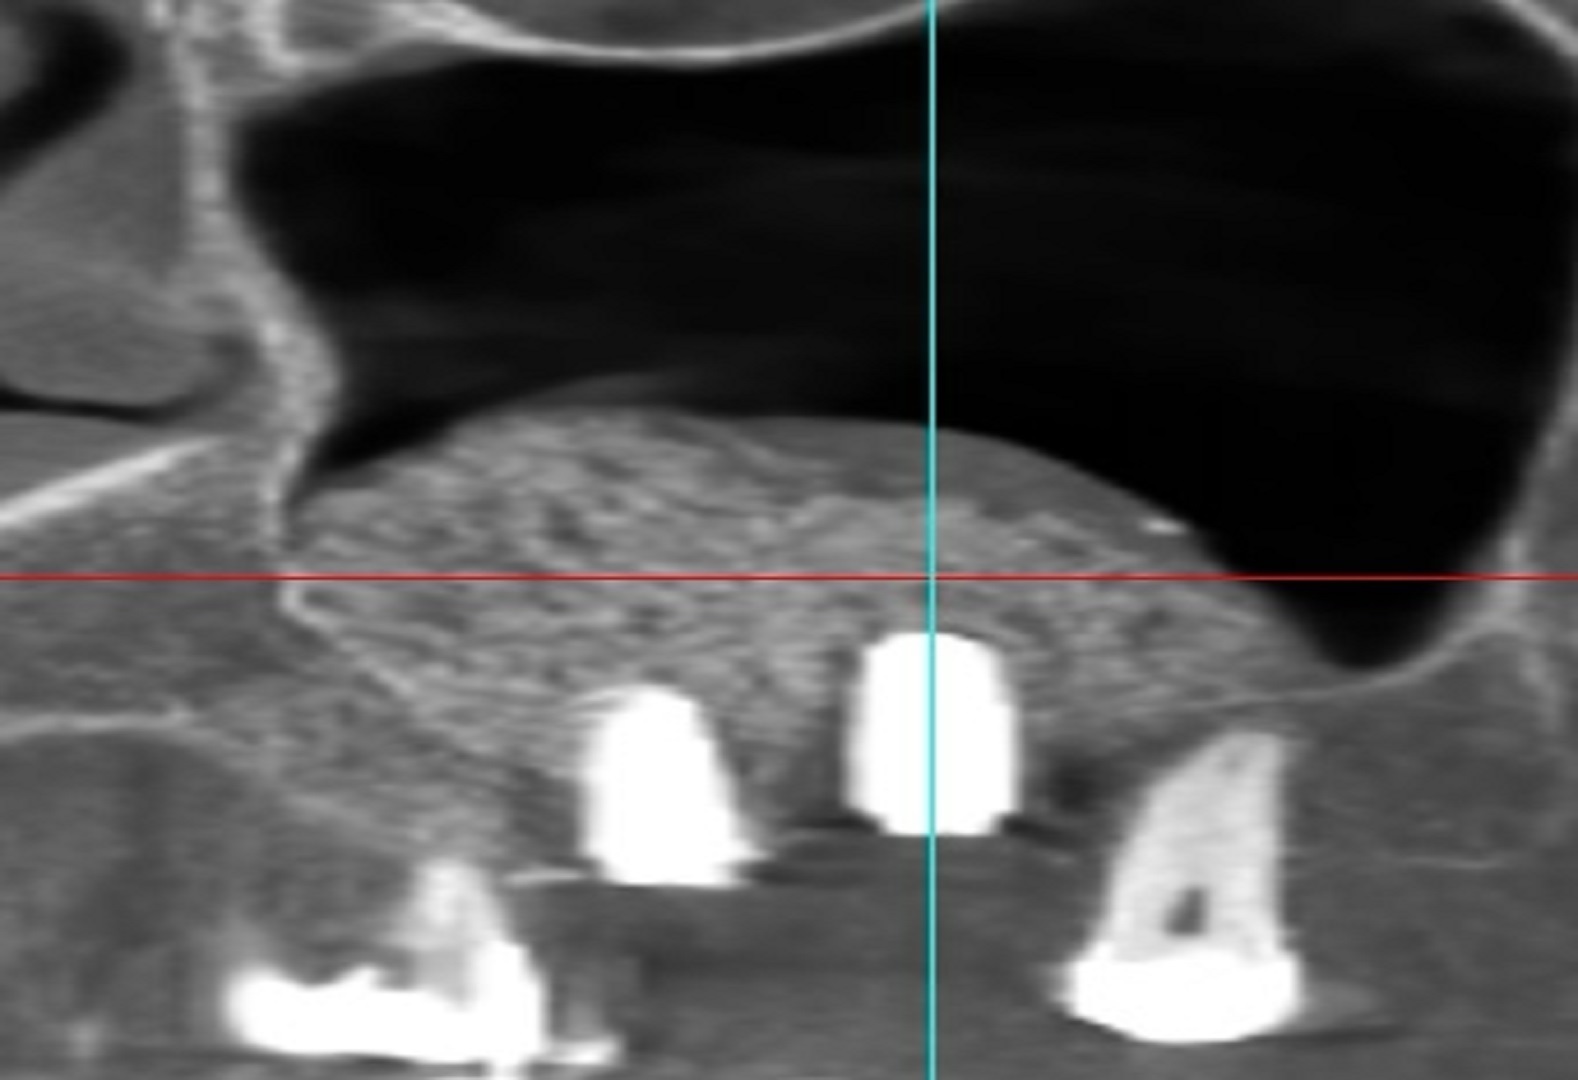

Le cliché 3D pré-opératoire révèle une cloison (ou refend) au sein du sinus maxillaire droit d’une patiente de 67 ans.

Le cliché 3D post-opératoire montre les deux implants vissés de part et d’autre du refend et dans la masse des deux comblements osseux réalisés indépendamment .